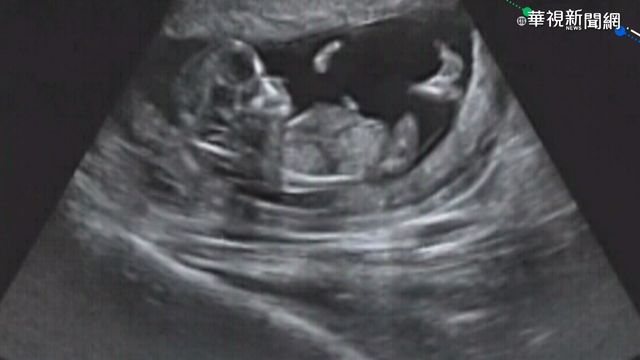

根據國健署最新數據,台灣7到15歲的兒童,有五萬多名患有氣喘,7千多名有心臟病。至於其他慢性病,有近三成兒童體重過重,一成有空腹血糖異常問題,每1000位就有2位有糖尿病。慢性病兒童,一旦因病請假,常常影響學習,國健署現在透過個案管理,密切掌握孩童健康。